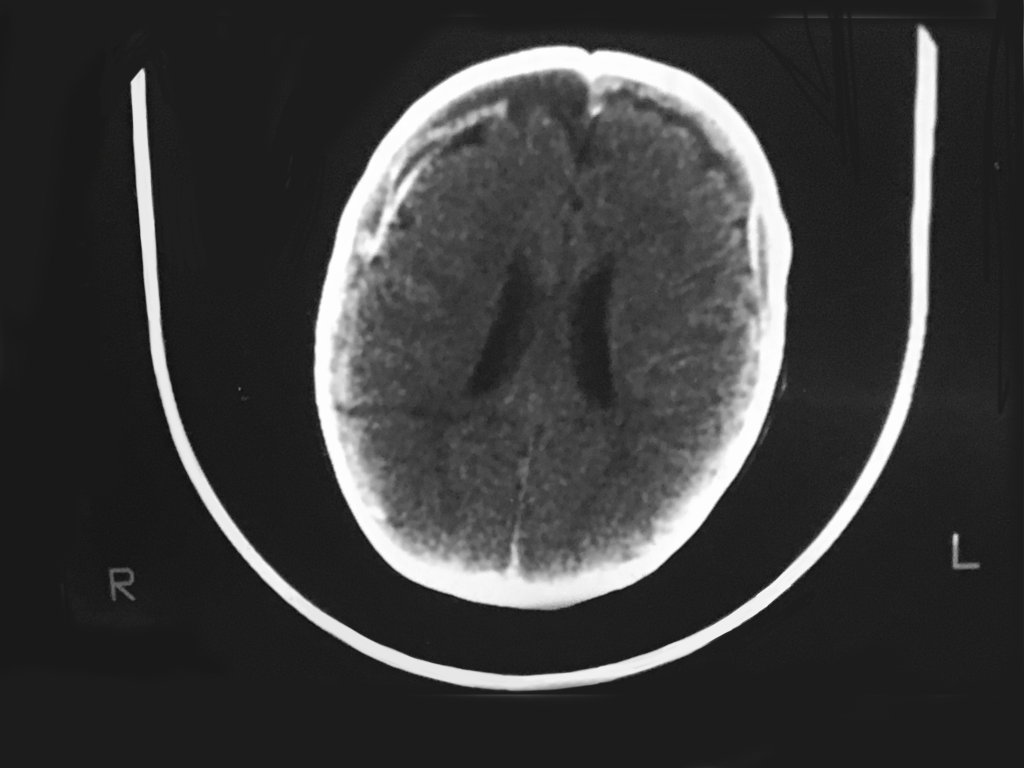

Test Item 2/multiole questions:  What is the diagnosis?  Describe all of the findings.  Is this a pathognomonic study?  What is all the indicated management?

CT findings:  Bilateral frontal old SDHs seen as loss of bifrontal cortical gray matter with bifrontal hygromas; acute Rt frontal SDH [white crescent on right], brain laceration on right deep within the substance of the brain [dark horizontal line rt posterior]; dilated ventricles = increased intracranial pressure.

Test Item 2 Answers:  Dx:  This CT [-} study is pathognomonic for shaken baby syndrome!!